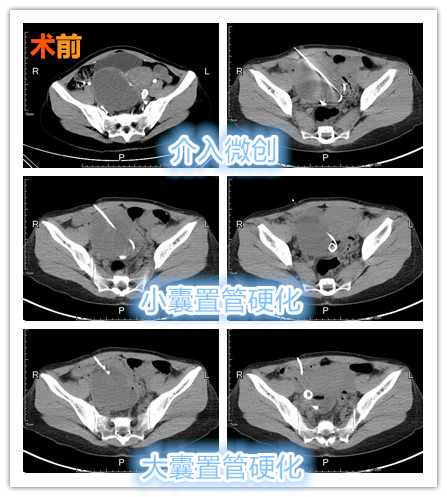

中年女性患者,发现巨大巧克力囊肿3年余,近期腹痛、腹胀感有所加重。术前CT提示巨大巧囊内出现分隔,术中先穿刺较小分隔囊腔,置管引流管冲洗硬化治疗,后续置管较大分隔囊腔留置引流管术后持续冲洗硬化治疗,达到一次穿刺治疗双囊腔效果。

一针双囊

介入微创守护女性健康!